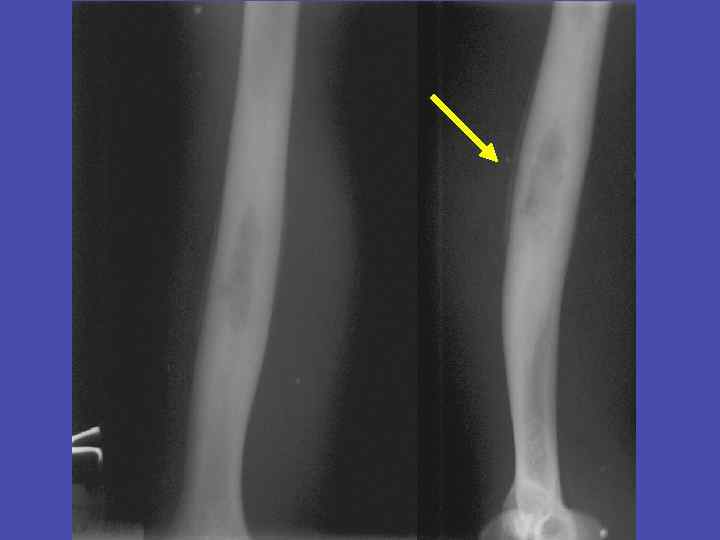

Линейный периостит большеберцовой кости 31

Линейный периостит, деструкция метадиафиза, перфорационные отверстия большеберцовой кости 34

Периостит, деструкция метадиафиза, перфорационные отверстия плечевой кости 35

Перфорационные отверстия большеберцовой кости 36